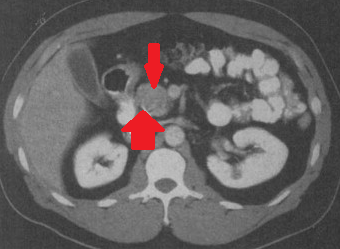

CT Angiography. Presence of a ruptured pseudoaneurysm of the common hepatic artery (Courtesy Dr. V. Penopoulos)